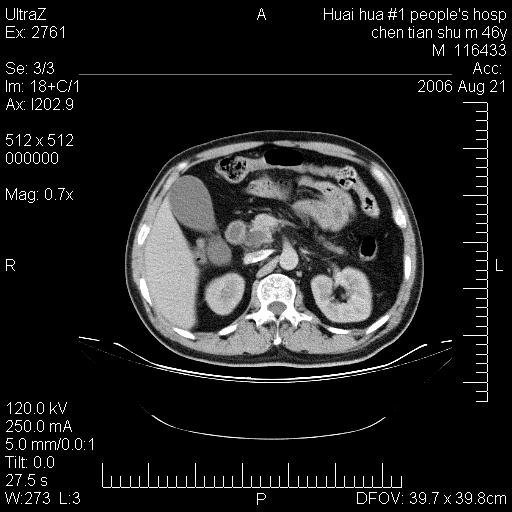

患者,男,46y。腹痛2月,消瘦。

手术病理结果:原发性小肠恶性淋巴瘤(primary gastrointestinal lymphoma,pgil)是原发于胃肠的淋巴网织系统的恶性肿瘤,在结外淋巴瘤中居第一位,该病少见,临床无特异性,诊断困难,术前主要依靠影像学诊断。胃肠道本身具有较丰富的淋巴组织,因而胃肠原发性淋巴瘤是结外淋巴瘤最常见的部位,文献报道约占胃肠道恶性肿瘤的1%~4%,其中胃约占50%~70%,小肠约占35%~70%,结肠约占4%~6%。影像检查在pgil的诊断及分期中有重要的作用,ct是很有价值的检查方法。

胃肠淋巴瘤病理特点:胃肠道原发性淋巴瘤起源于胃肠壁固有层和黏膜下层的淋巴组织即胃肠粘膜相关淋巴组织(malt),多为粘膜相关淋巴瘤。病理上通常为非霍奇金淋巴瘤,且决大多数来源于b淋巴细胞,很少见于霍奇金淋巴瘤。胃肠原发淋巴瘤比胃肠道癌的发病率要低的多,最常见于胃,其病因可能跟幽门螺杆菌感染有关。幽门螺杆菌能引起胃粘膜损害,引起炎性及免疫反应,淋巴细胞聚集并形成滤泡,可影响胃的正常生理功能,导致胃淋巴瘤的发生。单纯性小肠淋巴瘤是常见好发于回盲末端,受累的肠段较长,可单发、多发,甚至累及整个小肠。原发性大肠淋巴瘤罕见,以直肠和盲肠最多见。病变大体观可表现为胃肠腔内外的肿块,也可表现为从黏膜下到浆膜面肠壁的纵向浸润,并且常常伴有肠系膜淋巴结肿大。任何情况下,肿瘤几乎总是导致一定程度的肠壁增厚,可对称或不对称,病变与正常组织间常无明确分界,肠腔可狭窄、正常或动脉瘤样扩张,后者主要是肿瘤在肠壁内浸润,破坏肠壁内植物神经丛所致。以上改变成为ct检测病变的病理基础。

肠道淋巴瘤的ct表现分为4类

1) 壁内浸润型, (2)多发结节型, (3)肠系膜受累伴腔外肿块型(本型就是),(4)肿块型。